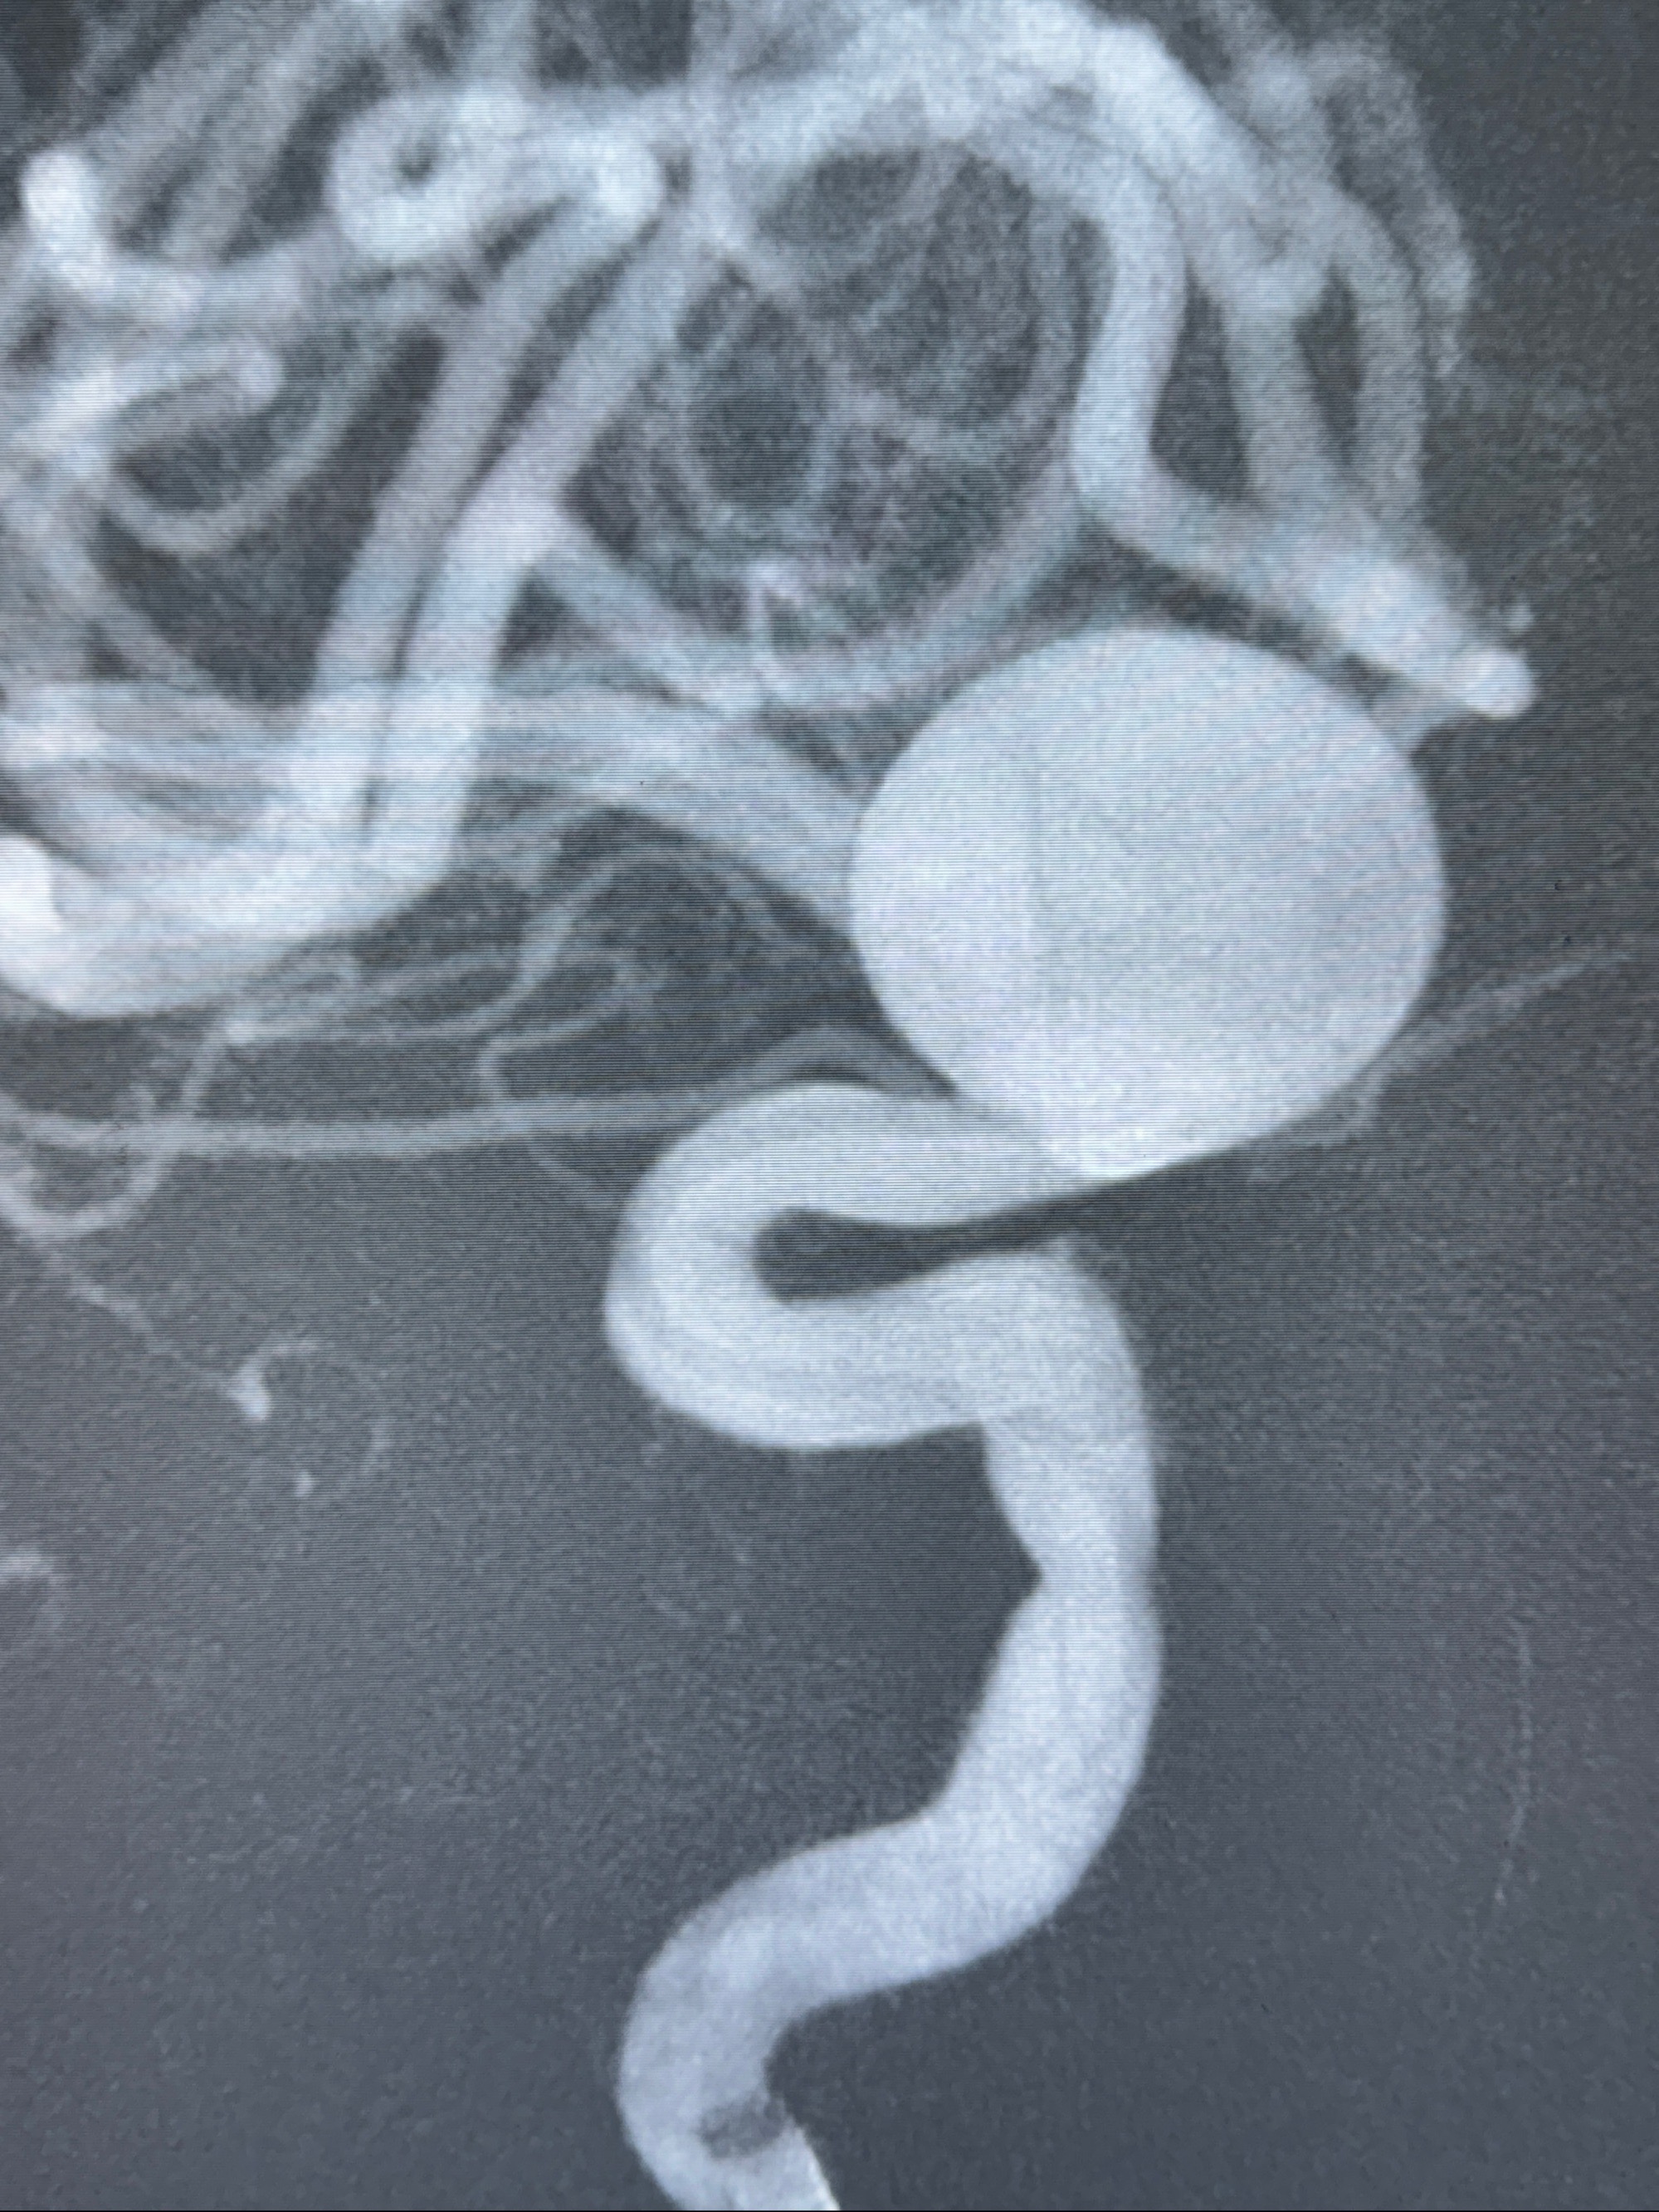

2023-12-27术后第十天复查DSA

支架贴壁佳,但可见射流,咋办?

2024-01-08全麻下再行植入密网支架一枚

Tubridge 4.5-35mm

支架植入顺利,贴壁佳,支架内血流通畅,动脉瘤内血液滞留明显